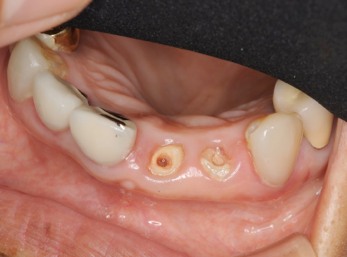

右の前歯二本がボッキリおれてしまいました。幸い歯の根っ子は折れていませんでしたから、抜歯せずに残せそうですが.........

歯が折れて根っ子が少しだけ歯茎からでている状態。

虫歯でもそうですが、こうなるとこのまま差し歯をいれてもすぐ外れるといったトラブルが起こります